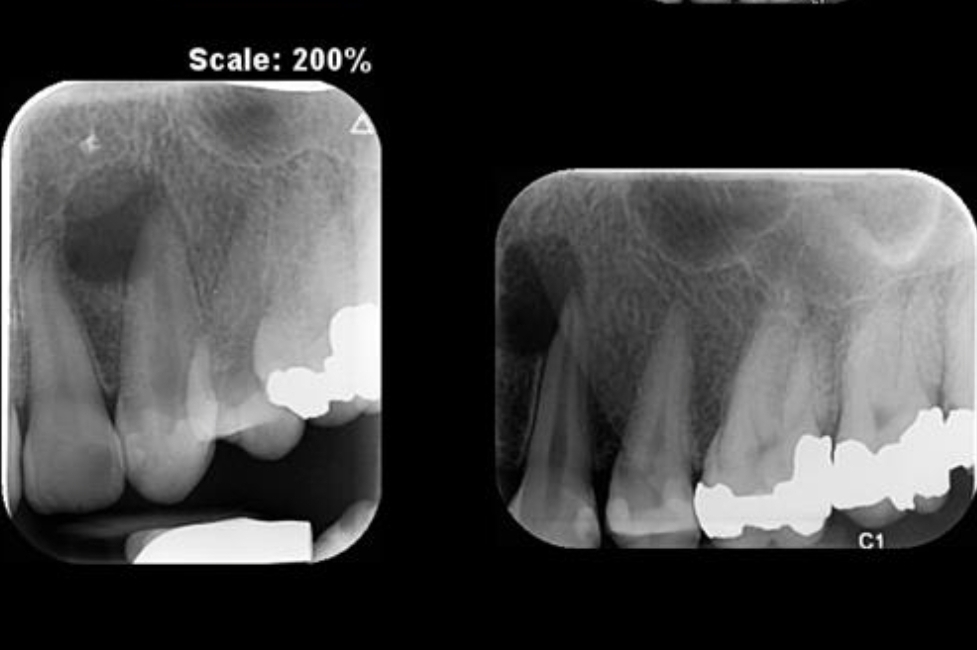

۳. نقش رادیوگرافی و CBCT

رادیوگرافی معمولی (Periapical X-ray): ابزار اصلی و اولیه است ولی دو بعدی بودن آن محدودیت دارد.

مطالعات نشان داده‌اند که CBCT نسبت به رادیوگرافی معمولی حساسیت بالاتری در شناسایی ضایعات آپیکال دارد (Patel et al., IEJ 2009).

• وضعیت پری‌آپیکال قبل از درمان: ضایعات کوچک‌تر و محدودتر → پیش‌آگهی بهتر.

• پیگیری بیمار: مراجعات دوره‌ای برای ارزیابی رادیوگرافیک و کلینیکی و بررسی موفقیت درمان ضروری است.